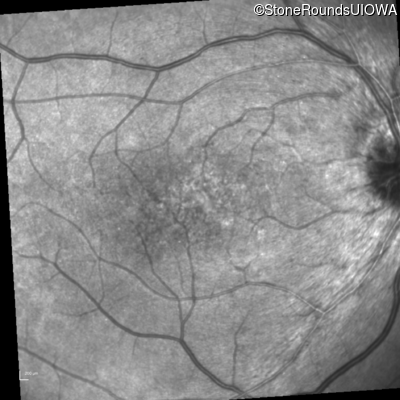

Infrared Fundus Photograph - Right - 20/30 -1

Exemplar